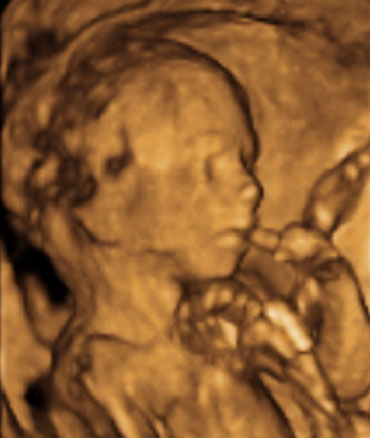

En esta ecografía en 4D se distingue el escroto de este feto varón. En la ecografía de la 20 semanas de embarazo, es muy probable que la embarazada ya sepa el sexo de su bebé, ya que se puede ver en la semana 12. No obstante, ahora se confirma.

Ultrasonido del aparato genital masculino en tres dimensiones

Las imágenes dan buena cuenta del sexo del bebé: se aprecia la pierna, el escroto, el pie y el cordón umbilical de la criatura.